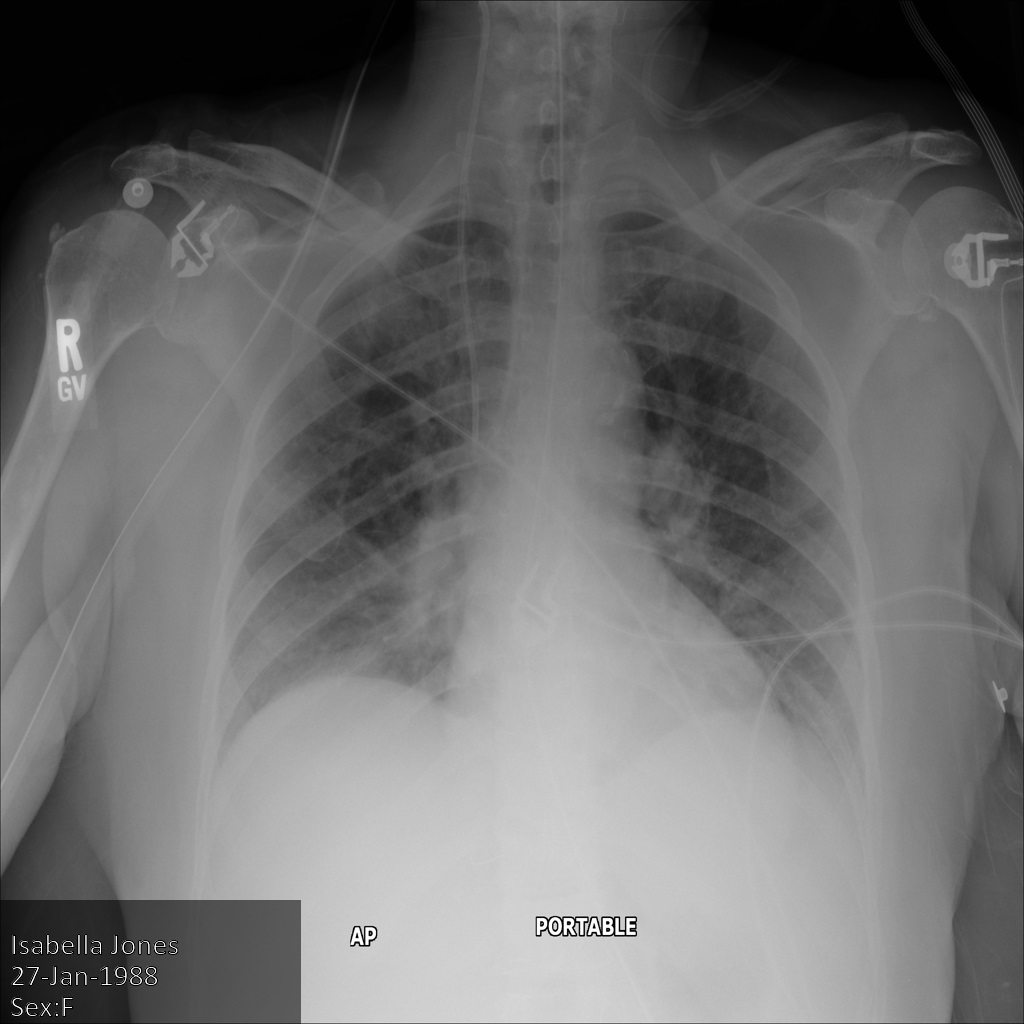

下图显示了未经遮盖的患者 X 光片:

xray2_unredacted

使用 REDACT_SENSITIVE_TEXT 选项将图片提交到 Cloud Healthcare API 后,图片显示如下:

xray2_redact_sensitive_text

您可以看到以下情况:

• 图片左下方的 PERSON_NAME 已被遮盖

• 图片左下方的 DATE 已被遮盖

根据默认 DICOM infoType,该患者的性别不属于敏感文本,因此未遮盖。